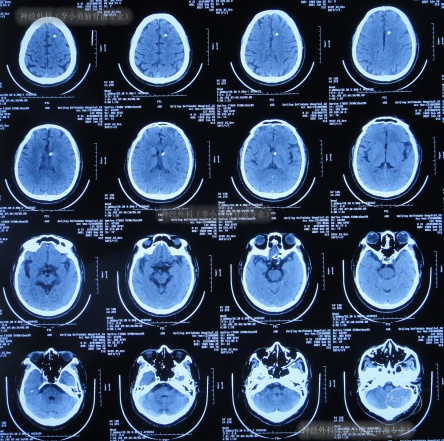

出院后3余年即2020年10月21日,第2次出现行走不稳,头晕;于是第2次就诊给予脑室腹腔分流术的医院,就诊期间出现嗜睡,查头颅CT(图-1)后给予调高分流泵压。

图-1:2020年10月21日头颅CT